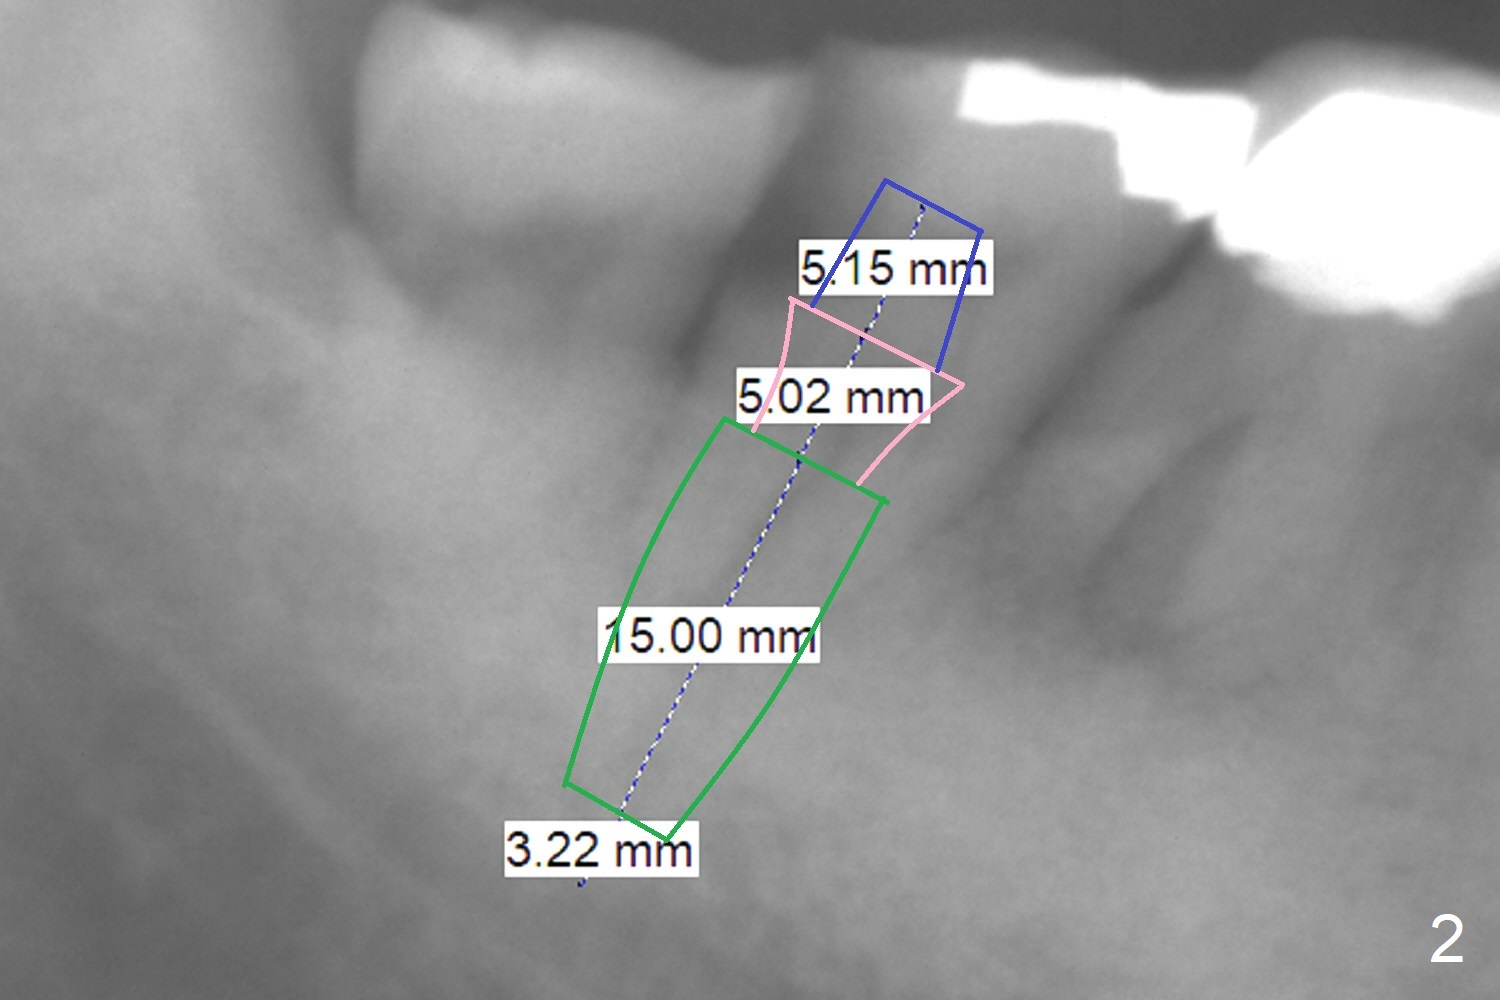

A 72-year-old man has DO subgingival caries (Fig.1 *). He prefers implant over RCT (Fig.2). The tooth #30 has deep pocket or an abscess distlbuccally. Cavitron scaling will be done.